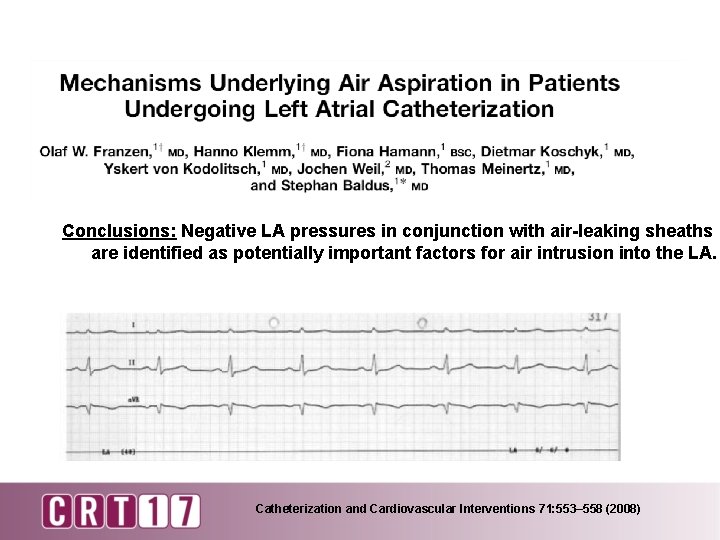

Conclusions: Negative LA pressures in conjunction with air-leaking sheaths are identified as potentially important factors for air intrusion into the LA. Catheterization and Cardiovascular Interventions 71: 553– 558 (2008)